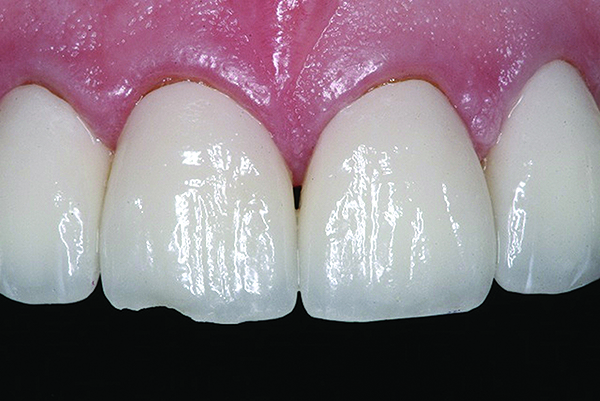

Figure 5 and Figure 6. All-ceramic restorations (Figure 5) and opposing dentition wear (Figure 6) produced by all-ceramic feldspathic restorations.

Figure 5